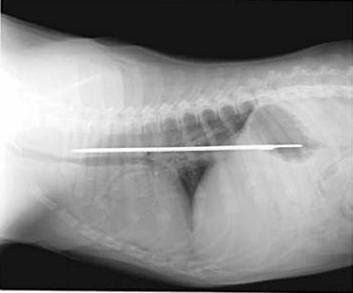

11. Anjing penelan pisau

Seekor Saint Bernard menelan pisau 13-inch pada tahun 2005. Dia baik-baik saja setelah operasi dan kejadiannya hanya meninggalkan bekas luka 8-inci.